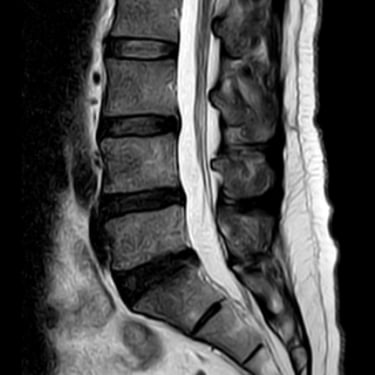

Discopatía Lumbar Degenerativa con Artrosis Facetaria | Diagnóstico por Resonancia Magnética

La discopatía lumbar degenerativa con artrosis facetaria es una causa frecuente de dolor lumbar crónico, que limita la movilidad y la calidad de vida del paciente. Esta condición combina la degeneración de los discos intervertebrales con el desgaste de las articulaciones facetarias, lo que puede generar inestabilidad y compresión nerviosa. La resonancia magnética (RMN) es la herramienta diagnóstica más precisa, ya que permite identificar deshidratación y colapso discal, hipertrofia facetaria, estenosis foraminal y signos de inflamación. El diagnóstico temprano es fundamental para establecer un tratamiento adecuado, que puede ir desde medidas conservadoras hasta técnicas quirúrgicas mínimamente invasivas.